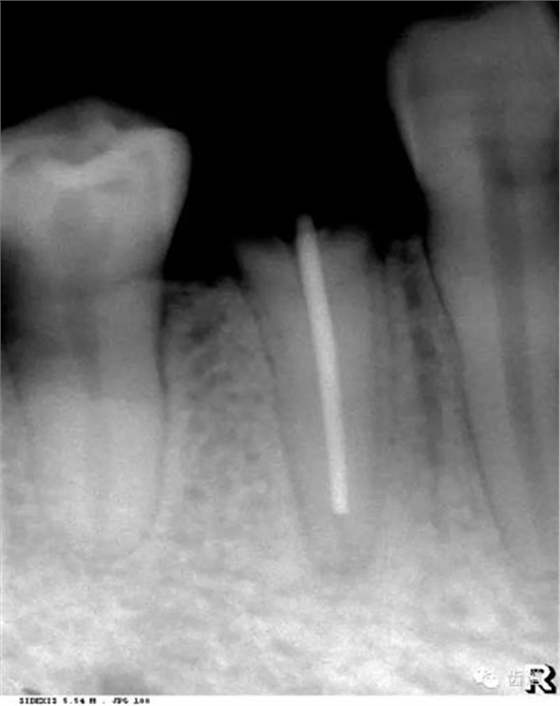

是介于牙槽窩和牙骨質(zhì)之間的結(jié)締組織。牙周膜的厚度一般在0.15~0.38mm之間。X線上顯示為包繞牙根連續(xù)不斷的密度低的線條狀影像,其寬度均勻一致